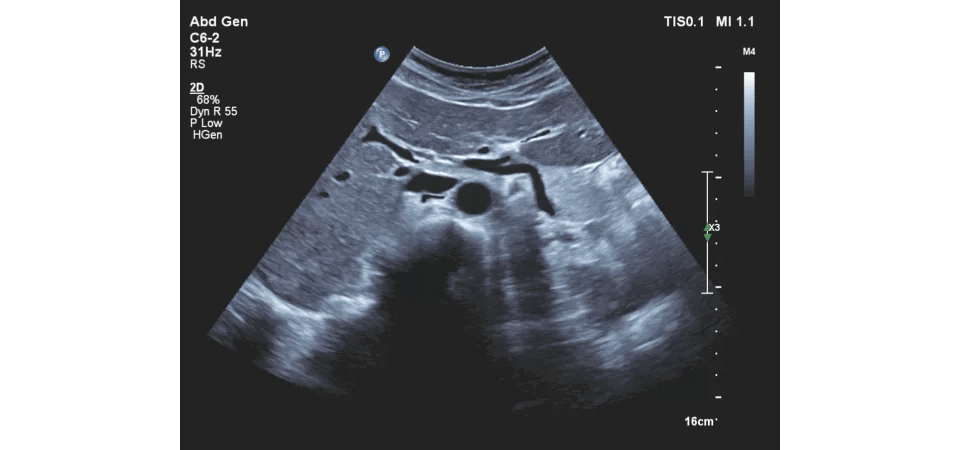

Vroegtijdige detectie van galstenen, nierstenen, cystes, myomen, of zwangerschap.

Beoordelen van buikklachten of pijn in de onderbuik zonder eerst naar een specialist te verwijzen.

• opsporen van vocht in de buik of longen

• beoordelen van spier- of peesproblemen